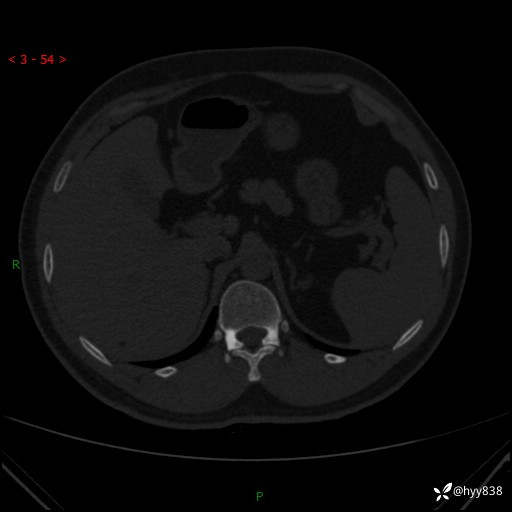

患者性别:男

患者年龄:28岁

简要病史:右肾肿瘤术后,常规复查

辅助检查:CT

临床诊断:右肾肿瘤术后

腹部CT+颅脑CT平扫